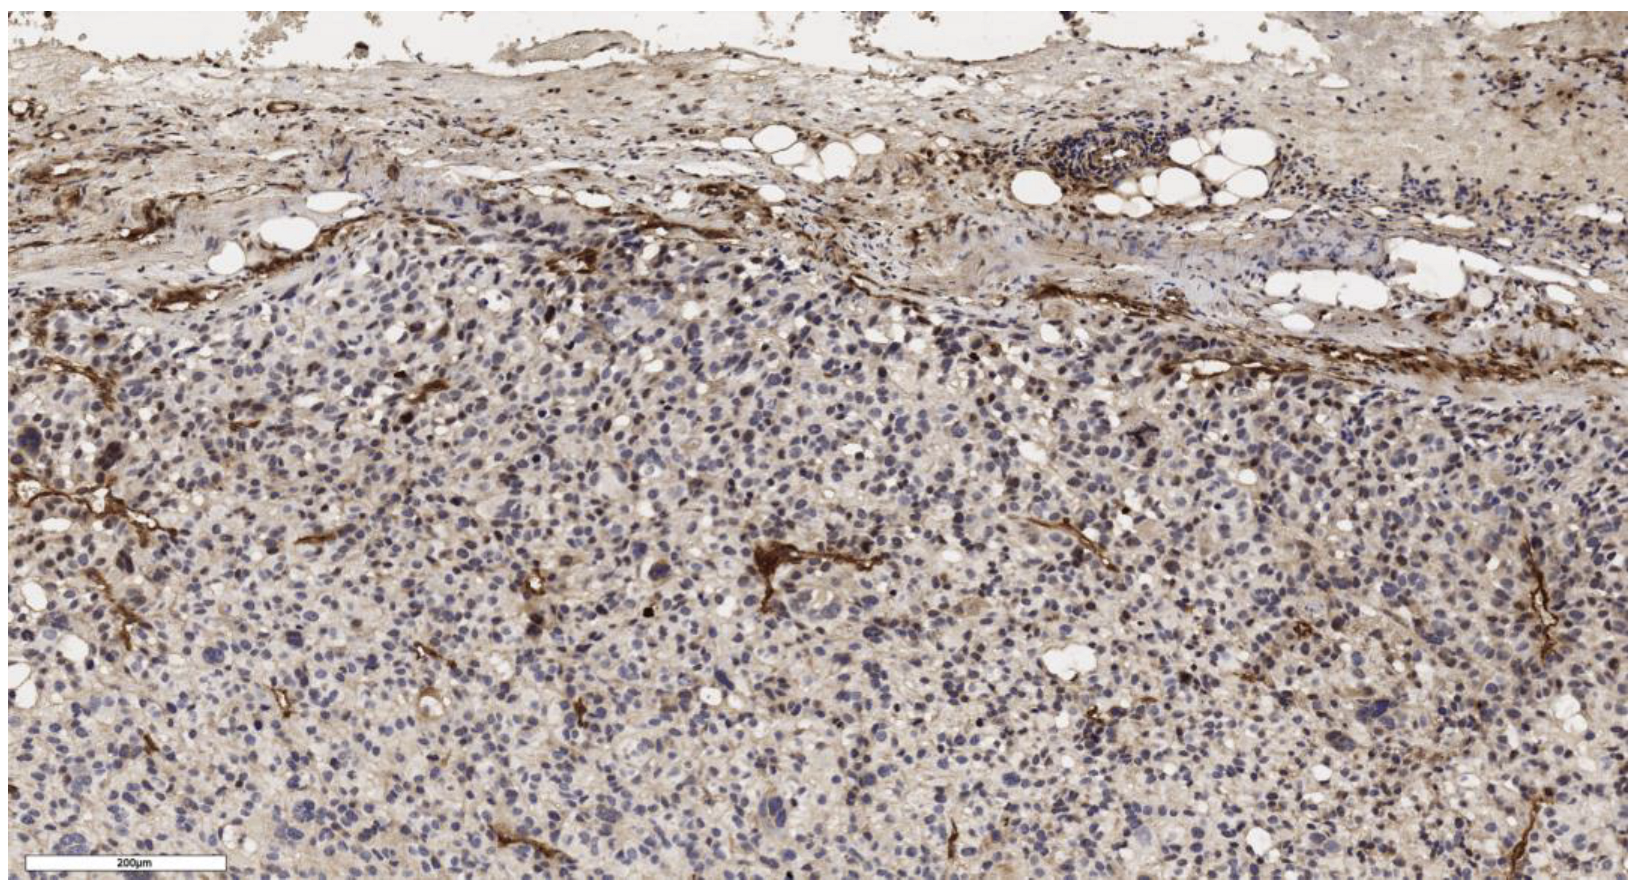

3.1. Analysis of CD90 Marker Expression